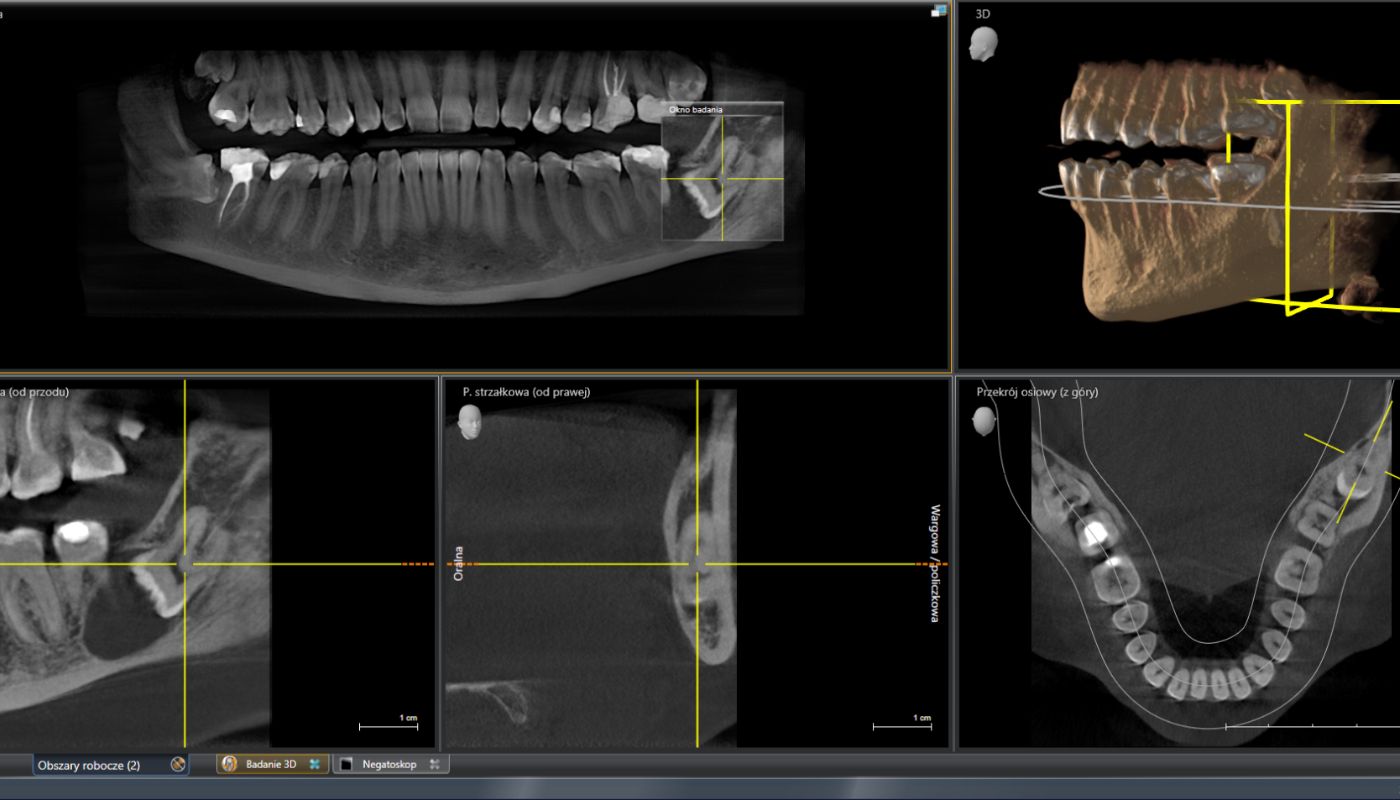

Zanim nastąpi usunięcie zęba, konieczne jest przeprowadzenie pełnej diagnostyki czyli RTG lub tomografii komputerowej CBCT. Zdjęcia pozwalają dokładnie zobrazować warunki anatomiczne pacjenta, stan zęba oraz kierunek jego położenia wraz z korzeniami.

Ma to na celu zapobiegnięcie przechylania się zębów po zakończeniu leczenia ortodontycznego oraz ułatwienie procesu prostowania zębów. Jest to szczególnie wskazane, gdy na obrazie radiologicznym jest wyraźnie widoczny ucisk ósemek na pozostałe zęby.